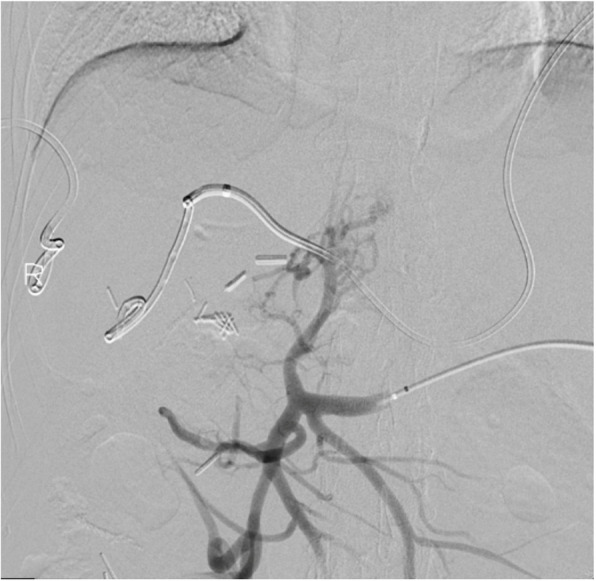

腹腔镜胆囊切除术治疗急性胆囊炎是最常用的手术之一,通常被认为是一种安全的手术,并发症风险低。血管和胆道损伤很少见,但后果严重。目前还没有进行系统的研究来描述这些情况下的最佳治疗策略,这些策略通常是根据具体情况进行管理的。本报告描述了一例患者行腹腔镜胆囊切除术,并发胆总管和门静脉主干结扎,导致肝梗死、肝周脓肿、门静脉高压合并腹水和门脉性充血性肠病。本病例的重点是处理该患者的血管损伤,并成功地通过经脾和右颈内静脉进入血管内门静脉重建。

Laparoscopic cholecystectomy for acute cholecystitis is one of the most performed surgeries and is generally regarded as a safe procedure with a low risk of complications. Vascular and biliary injuries are rare but have severe consequences. No systematic studies have been performed to delineate optimal treatment strategies in these scenarios, which are typically managed on a case-by-case basis. The present report describes a patient who underwent a laparoscopic cholecystectomy, complicated by common bile duct and main portal vein ligation, resulting in hepatic infarcts, perihepatic abscess, and portal hypertension with ascites and portomesenteric congestive enteropathy. This case focuses on management of this patient's vascular injury, which was successfully treated by endovascular portal venous reconstruction using trans-splenic and right internal jugular vein access.